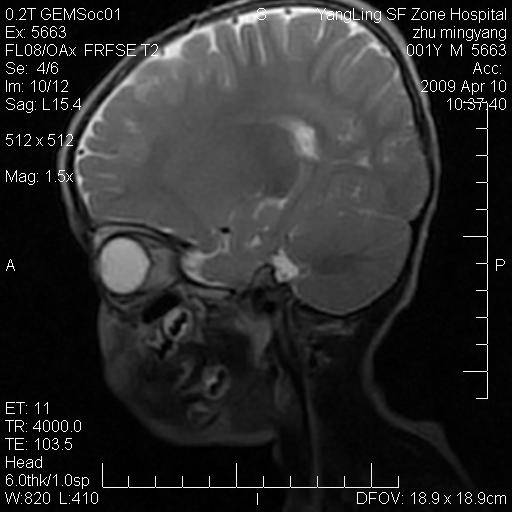

患者:1岁半,两天前外伤收住我院,ct检查小脑占位

考虑星形细胞瘤,建议增强

髓母细胞瘤或血管母细胞瘤,增强后可以鉴别;影像资料见 <。鱼博浪老师的《中枢神经系统ct与mr鉴别诊断》 小脑部肿瘤章节。

髓母细胞瘤或血管母细胞瘤!支持!

支持考虑髓母细胞瘤

考虑----髓母细胞瘤可能性大

考虑髓母细胞瘤或室管膜瘤。

支持髓母细胞瘤。

考虑髓母细胞瘤。

考虑髓母细胞瘤或星形细胞瘤

考虑髓母细胞瘤.

考虑髓母细胞瘤可能性大。

小脑肿瘤.考虑髓母细胞瘤可能.

就病灶部位及临床资料首先考虑髓母.